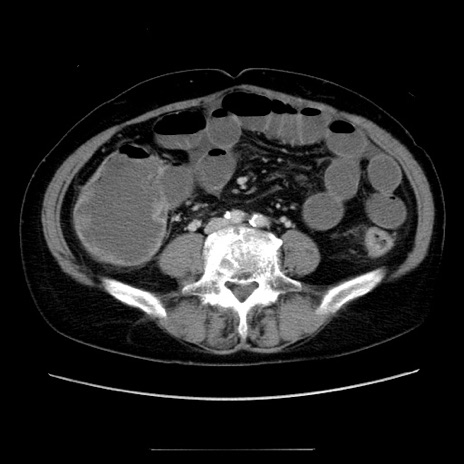

冠状断像

【症例】70歳代女性

【主訴】お腹が張る

【現病歴】1週間くらい前から腹部膨満の自覚あり。昨日夜から増悪したため、本日救急外来受診。

【身体所見】意識清明、BT 36.5℃、BP 165/106mmHg、HR 80bpm、SpO2 98%、腹部:膨満、軟、自発痛・圧痛なし、触診にて不快感あり、腸蠕動音:減弱

【データ】WBC 12600、CRP 1.04